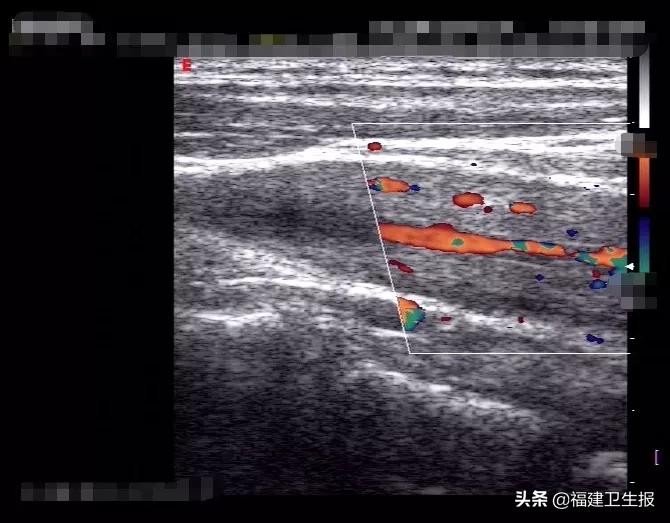

吴女士左侧颈动脉根部血管腔狭窄、壁增厚